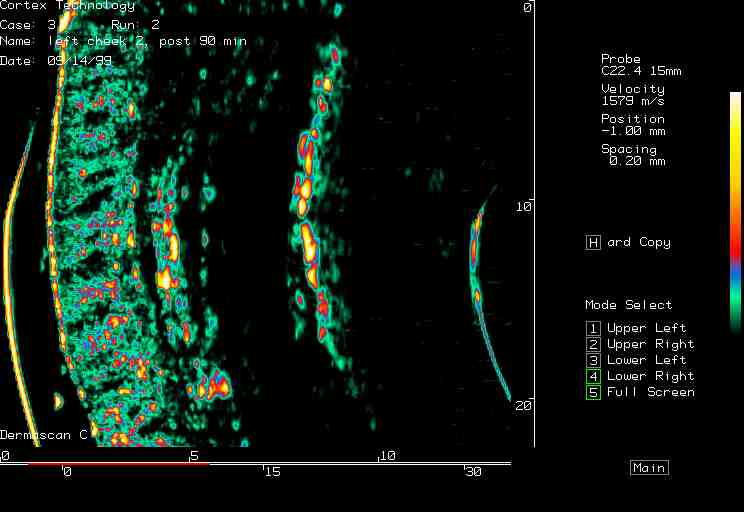

| Shaving reactions |  Cheek, prior to shaving |

Cheek, 0 min post shaving |

Cheek, 90 min post shaving |